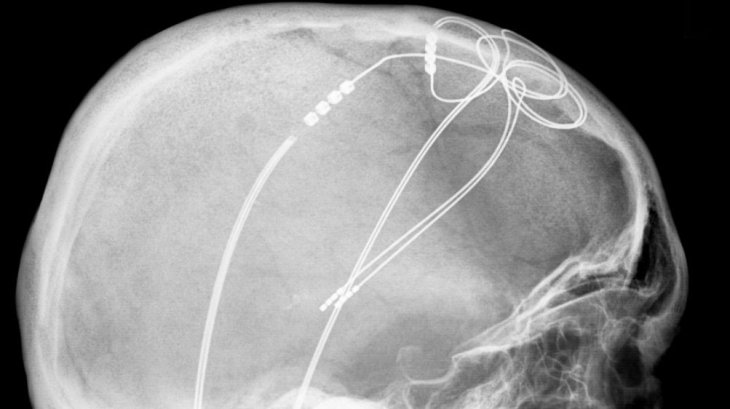

Usually, doctors use DBS to monitor neurological conditions such as epileptic seizures and Parkinson disease. Each condition is caused by erratic electrical activity in a specific area of the brain; in DBS, doctors implant electrodes in the patient’s brain through surgery and control them with a device implanted in the body, send impulses via these electrodes.

The implants will record the activity of the neural network within a targeted brain area, from which doctors can then identify the source of the patient’s seizures. Next, they can make a plan to safely remove the brain parts that are affected later. But in this experiment, they could make use of the same implants to mimic a DBS session.